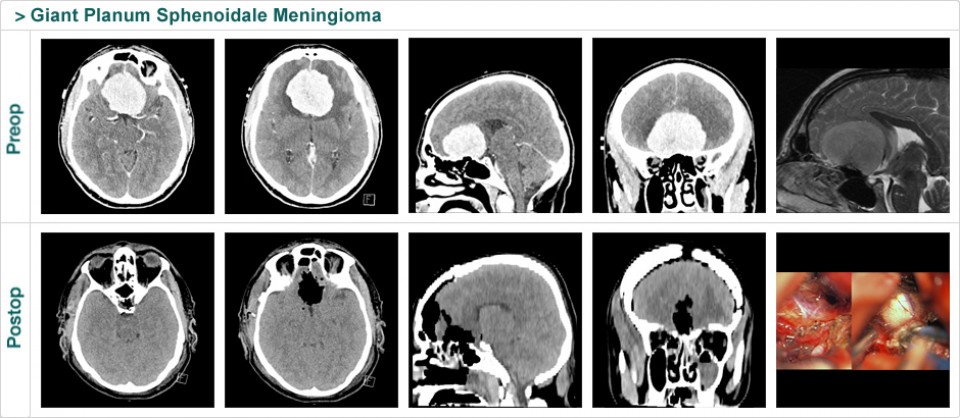

Dr. Attia is an attending neurosurgeon and the director of skull base surgery service in the department of neurosurgery at Sheba Medical Center in Tel HaShomer. His specialty focuses on skull base and cerebrovascular neurosurgery.